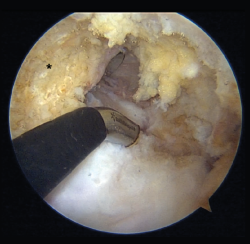

Arthroscopic portals

Depending on the preferences and experience of the surgeon, reconstruction of the PCL can be made through different portals. The standard anteromedial and anterolateral portals are routinely used for joint revision surgery and the treatment of associated chondral, ligamentous or meniscal lesions. Some authors use posteromedial and posterolateral portals to adopt a trans-septal approach (Kim's technique) and thus work exclusively from the back of the knee. Other surgeons prefer a portal through the patellar tendon (Gillquist portal) in combination with a posteromedial portal, alternating them as viewing and working portal. Utilization of the transpatellar portal is simpler in the case of combined rupture of the ACL and PCL, since the intercondylar space is completely vacant (Figure 8)(23).

Figure 8. "Vacant" intercondylar space in combined rupture of the anterior cruciate ligament (ACL) and the posterior cruciate ligament (PCL) in a left knee. The surgeon is using the transpatellar (Gillquist) portal for viewing and the anteromedial portal for working with radiofrequency. The working cannula placed in a posteromedial portal can also be seen. The black asterisk indicates the lateral wall of the medial femoral condyle, as the femoral insertion site of the PCL.

In the case of isolated PCL rupture, 70° optics instead of the conventional 30° optics can be used to obtain a wider view from the anterior portals. Lastly, a reconstruction technique has been described that only uses the anterolateral viewing portal (through the intercondylar space with 70° optics) and the anteromedial working port - with no need for posterior portals. This latter technique requires specifically designed instruments, however; as a result, it is not widely used(23,24,25).